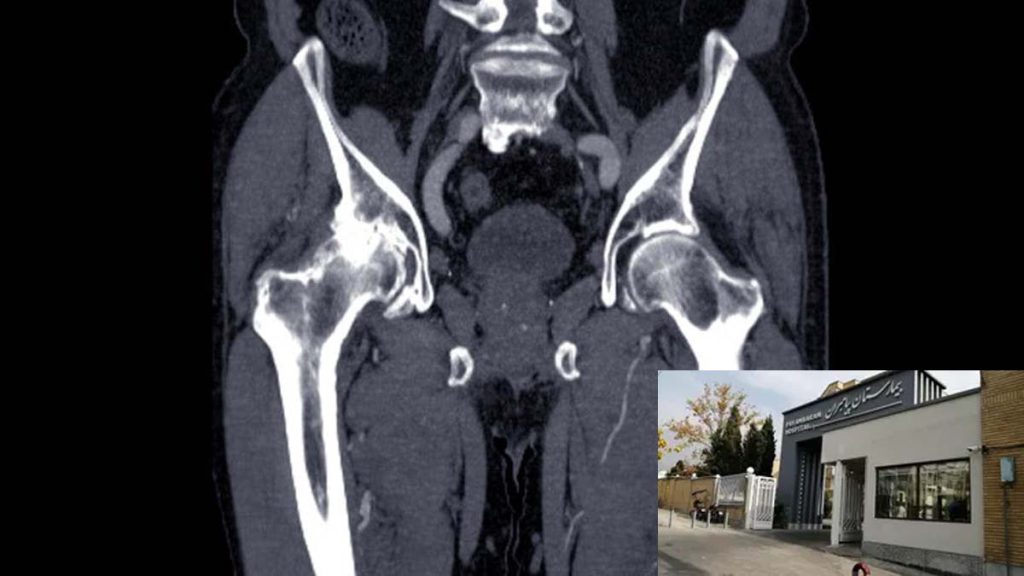

سی تی انژیو گرافی بیمارستان پیامبران یکی از پیشرفتهترین واحدهای تشخیص عروقی در ایران است. با بهرهگیری از تکنولوژی تصویربرداری بالا و تیم متخصص، این واحد قادر به تشخیص دقیق بیماریهای قلبی و عروقی، از جمله انسداد عروق کرونر، است. بیماران در این مرکز از خدمات سریع و دقیق بهرهمند میشوند و تمام تجهیزات پزشکی در سطح جهانی قرار دارد. بیمارستان پیامبران با تاکید بر بهبود کیفیت مراقبت، به عنوان یک مرجع معتبر در زمینه سی تی انژیوگرافی شناخته میشود. و کیفیت با رعایت کامل استانداردهای بینالمللی بسیار محسوب دارد.

A coronary angiogram can help your cardiologist look for blockages in your coronary arteries. X-ray images from your procedure will help your provider make a diagnosis and decide if you need medicine, a stent or surgery.

آنژیوگرافی عروق کرونر می تواند به متخصص قلب شما کمک کند تا به دنبال انسداد در عروق کرونر شما باشد. تصاویر اشعه ایکس از روش شما به ارائه دهنده شما کمک می کند تا تشخیص دهد و تصمیم بگیرد که آیا به دارو، استنت یا جراحی نیاز دارید یا خیر.

منبع: my.clevelandclinic.org